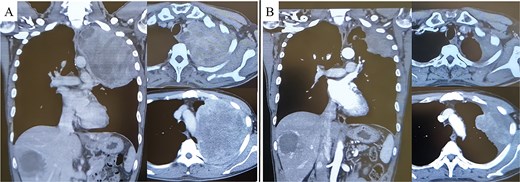

A 45-year-old male presented with left anterior chest pain. A chest X-ray revealed a mass in the left lung. Computed tomography (CT) showed a large tumor measuring 13 × 12 cm occupying the left thoracic cavity, with extensive invasion into the left first through fifth ribs and lung parenchyma. A CT-guided biopsy initially led to a diagnosis of sarcomatoid pleural mesothelioma, and the patient was referred to our hospital. The patient exhibited tumor-associated fever and elevated inflammatory markers. Treatment with nivolumab plus ipilimumab was initiated promptly. A re-evaluation of the biopsy specimen revealed proliferations of short spindle-shaped tumor cells. However, BAP1 was retained, MTAP status was inconclusive, and no CDKN2A/CEP9 probe deletion was observed, ruling out pleural mesothelioma. The final biopsy diagnosis was sarcoma. After four cycles of nivolumab plus ipilimumab, the tumor size significantly decreased (from 139 × 122 mm to 97 × 76 mm), leading to the decision to proceed with salvage surgery (Fig. 1A and B). Despite a 4-week interval between the final immunotherapy dose and the surgery, tumor regrowth was observed during this period (Fig. 2A–C).

Pre-treatment CT revealed a large mass exceeding 13 cm in the left lung apex, with invasion into the first through fifth ribs (A). Following treatment with nivolumab with ipilimumab, the tumor showed marked shrinkage (B).